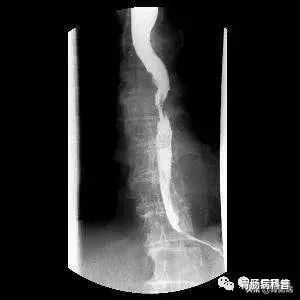

食管癌钡餐造影

1、消化道钡餐造影

仅在病变发生解剖形态学明显改变时才能显示出来,早期食管癌的诊断阳性率较低,准确率仅为50%左右,因此单纯X线造影不能独立作为早期食管癌的诊断方法。

造影有可能显示病变区黏膜皱襞增粗、迂曲、紊乱和中断,小溃疡龛影,小充盈缺损,局限性管壁僵硬。出现这些特征提示病变已非很早期,至少为早期浸润癌。